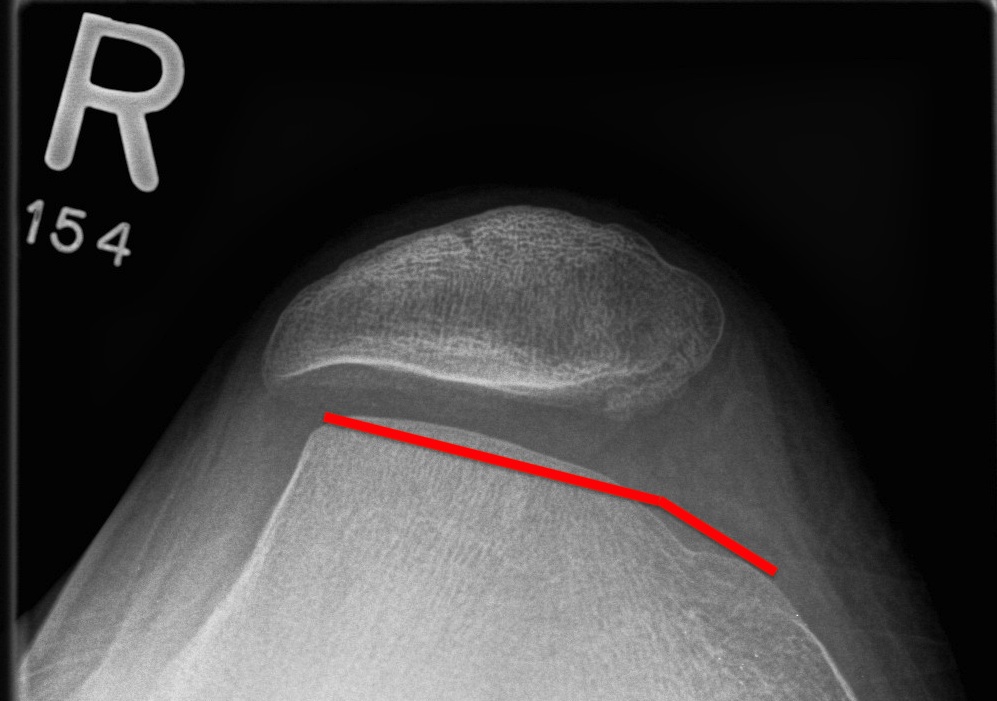

Trochlea dysplasia / Sulcus angle

- normal < 140o

- > 140o flattened

Normal trochlea / sulcus

Trochlea dysplasia